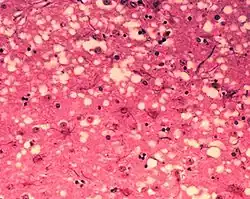

Prionii sunt agenți infecțioși nonconvenționali de natură proteică, lipsiți de orice tip de acid nucleic, care produc un grup de boli neurodegenerative transmisibile ale animalelor și omului, numite boli prionice (encefalopatii spongiforme transmisibile). Dintre acestea, cea mai cunoscută este encefalopatia spongiformă bovină (boala vacii nebune), dar există forme de encefalopatie spongiformă și la alte specii de animale: scrapia (la ovine și caprine), encefalopatia spongiformă a cervidelor etc. Din categoria bolilor prionice ale omului fac parte: boala Creutzfeldt-Jakob, insomnia fatală familială, boala Kuru, sindromul Alpers (la copil) etc.

Prionii formează agregate anormale de proteine numite amiloizi, care se acumulează în țesutul infectat și sunt asociate cu deteriorarea țesuturilor și moartea celulelor.[1] Amiloizii sunt, de asemenea, responsabili pentru câteva alte boli neurodegenerative, cum ar fi boala Alzheimer și boala Parkinson.[2][3] Agregatele prionice sunt stabile, iar această stabilitate structurală înseamnă că prionii sunt rezistenți la denaturare de către agenți chimici și fizici: nu pot fi distruși prin dezinfecție sau gătire obișnuită. Acest lucru face dificilă eliminarea și izolarea acestor particule.